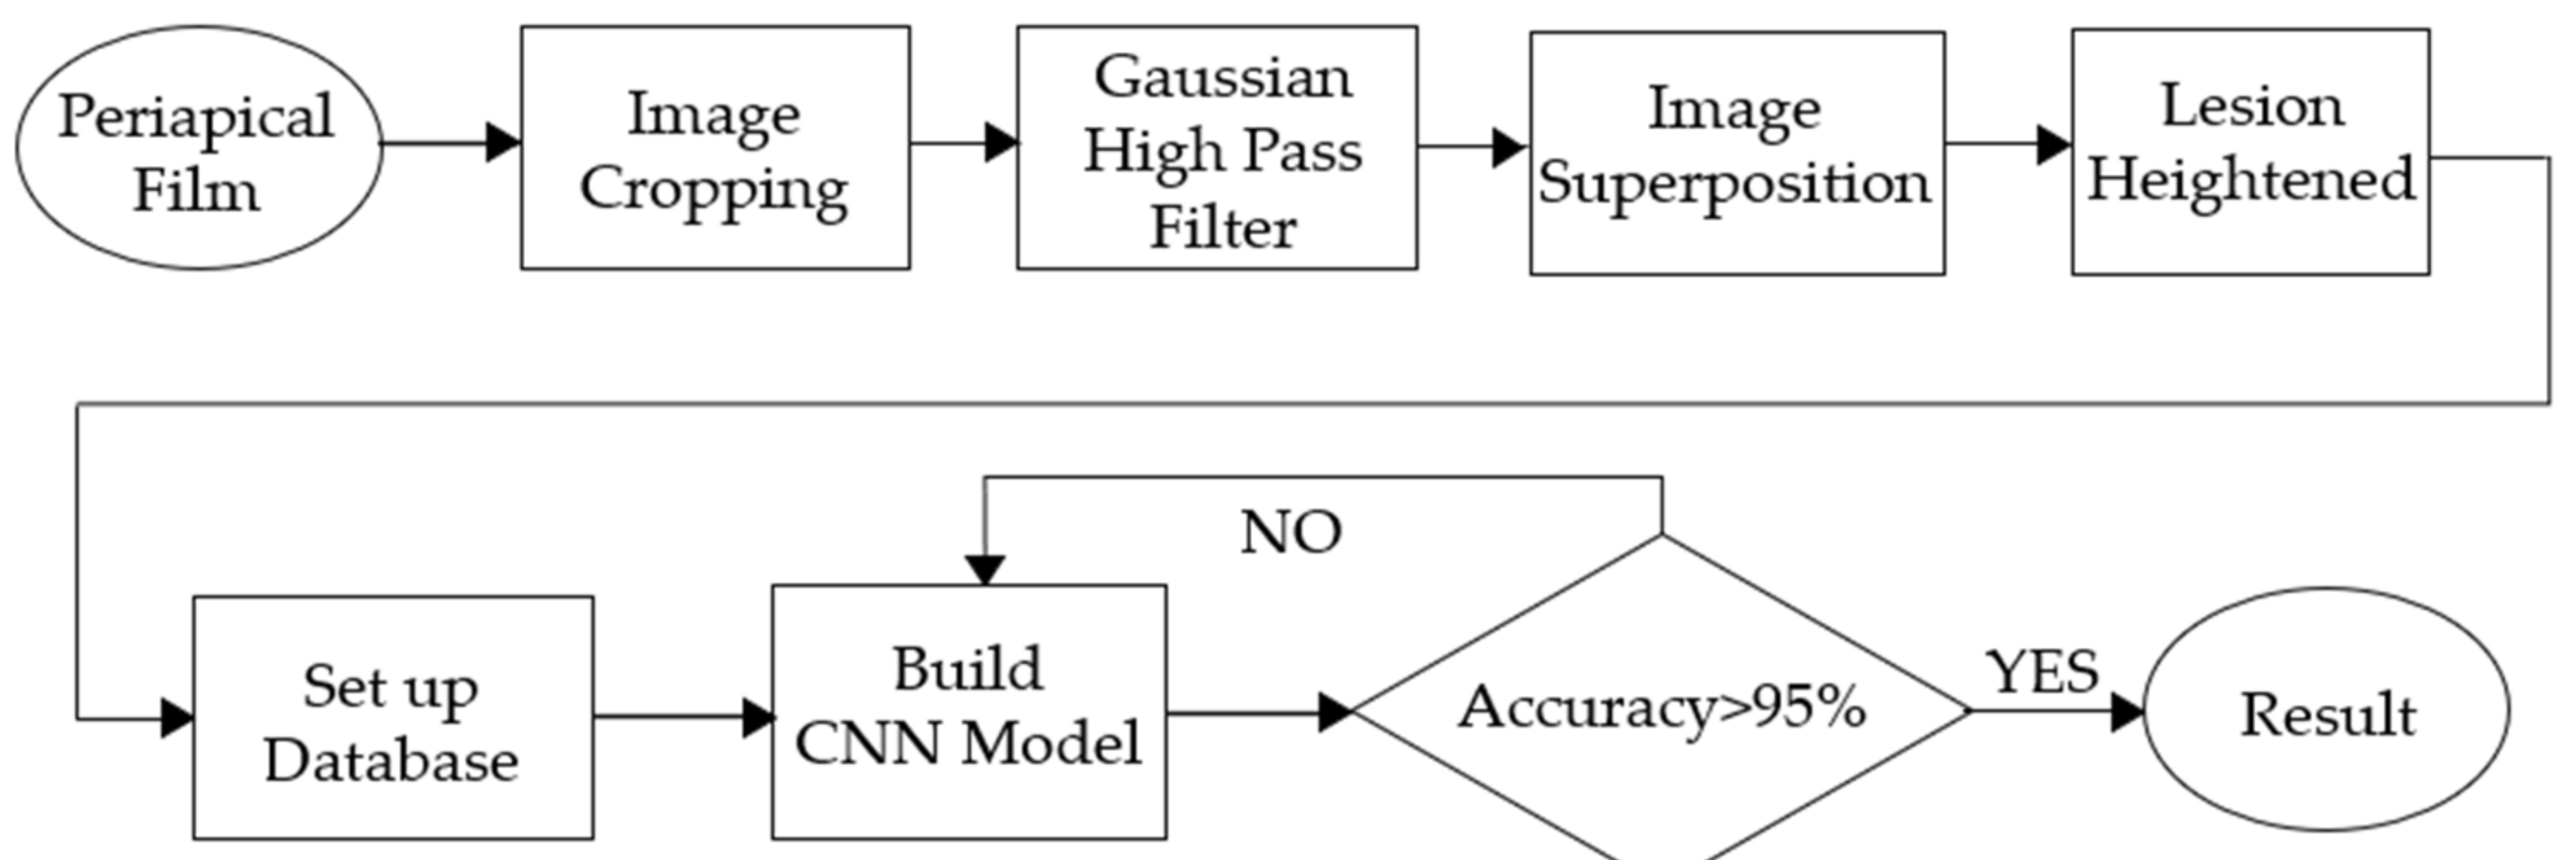

- In the image cropping preprocessing part, this study adds the adaptive threshold and angle rotation technology. Compared with the existing methods, this method significantly improves the image clarity and accuracy of a single tooth image.

2.1. Image Segmentation and Retouching

2.1.1. Vertical Cutting

2.1.2. Image Masks